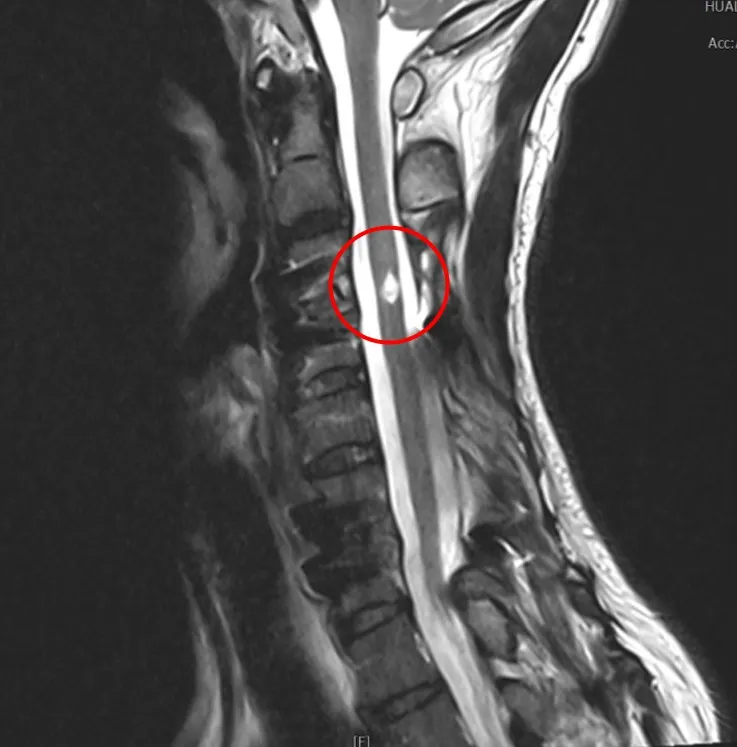

神經外科主任蔡昇宗表示,在脊椎適合位置植入神經刺激器,透過電極發送微量電流到神經節控制的相關肌肉群,能幫助嚴重腦損傷及脊髓損傷的患者,從意識不佳到逐漸清醒,讓全身癱瘓無法行走的病人再次站起來,並練習走路,促進病人生活自理的能力,找回生命的尊嚴,也減輕照顧者的壓力。

「能醒能走」是花蓮慈濟醫院神經外科中西醫復健合療團隊積極努力的重大發展方向,其中利用脊髓電刺激療法改善脊髓損傷病友的症狀,是花蓮慈院近三年來發展的技術重點之一。脊髓電刺激器植入(SCS)技術自一九七五年即問世,且已發展出常規手術,但最初主要是用在疼痛治療上;直到近年美國、瑞士醫界先後發表運用脊髓電刺激器植入(SCS)改善脊髓損傷癱瘓病人的肢體活動成果。

邱先生接受脊髓電刺激器植入手術至今已2年半,原先左腳神經控制較弱,電刺激器正好可以協助他在站立時的穩定性,再搭配高強度的手腳肌力、平衡感、耐力復健,達到一定的輔助效果。